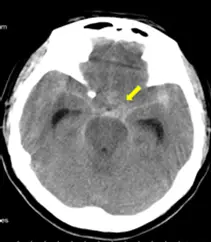

本題附圖為無顯影劑的腦部電腦斷層(Non-contrast Head CT)軸切面影像。圖中黃色箭號指出的位置為基底腦池(Basal cisterns)與左側外側裂(Sylvian fissure)周圍,可見明顯的高密度(Hyperdense)物質沉積。在無顯影劑的 CT 影像中,腦脊髓液所在的蜘蛛膜下腔若出現高密度訊號,即為典型的**急性蜘蛛膜下腔出血(Acute Subarachnoid Hemorrhage, SAH)**表現。此類出血最常見的非外傷性原因為顱內動脈瘤破裂(Ruptured intracranial aneurysm)。

- SAH 的 CT 影像特徵:蜘蛛膜下腔(包含基底腦池、外側裂、大腦鐮、大腦迴溝等)出現異常的高密度(Hyperdense)血液訊號。